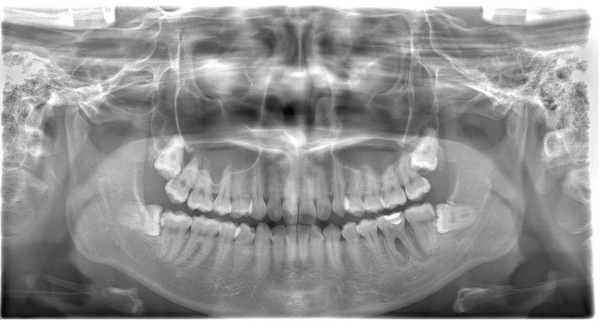

こちらが根管治療終了後のX線写真です。

治療開始時点で症状は和らいでおり、根管治療が終了した段階では完全に症状が消失しておりました。

通常であれば、ここから仮歯にて数カ月経過観察を行い、次の判断をしていきます。

今回は患者様のご都合もあり、最終的なセラミックの歯を仮止めする形での経過観察となりました。

こちらが根管治療終了後から1年3ヶ月後のX線写真です。

完全に骨が回復したと言って良い状況となりました。